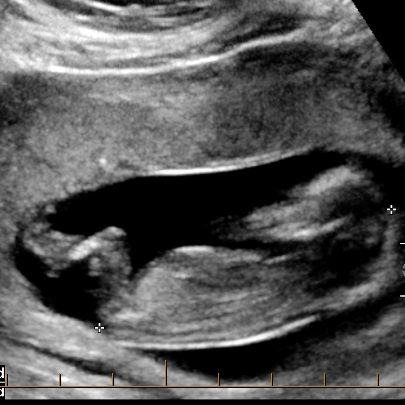

Potty shot looks girl but nub looks questionable

How many weeks is this? There is no hamburger in the first, and probably a penis in the second so I'm going for boy.

This was at 12w2d

Could definitely be either as it's a bit early for nub guessing

boy. Too early for a potty shot